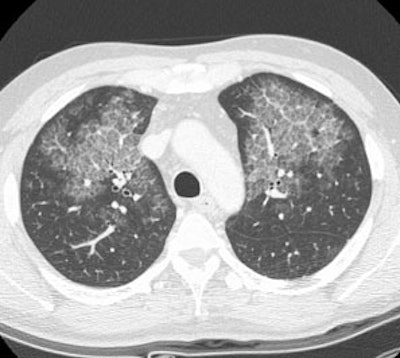

Alveolar Proteinosis:

The patient presented for evaluation of progressive shortness of breath. The CXR demonstrated bilateral perihilar infiltrates producing an appearance of pulmonary edema. HRCT exam revealed central areas of ground glass attenuation with underlying septal thickening producing a "crazy paving" appearance. Click images to enlarge.